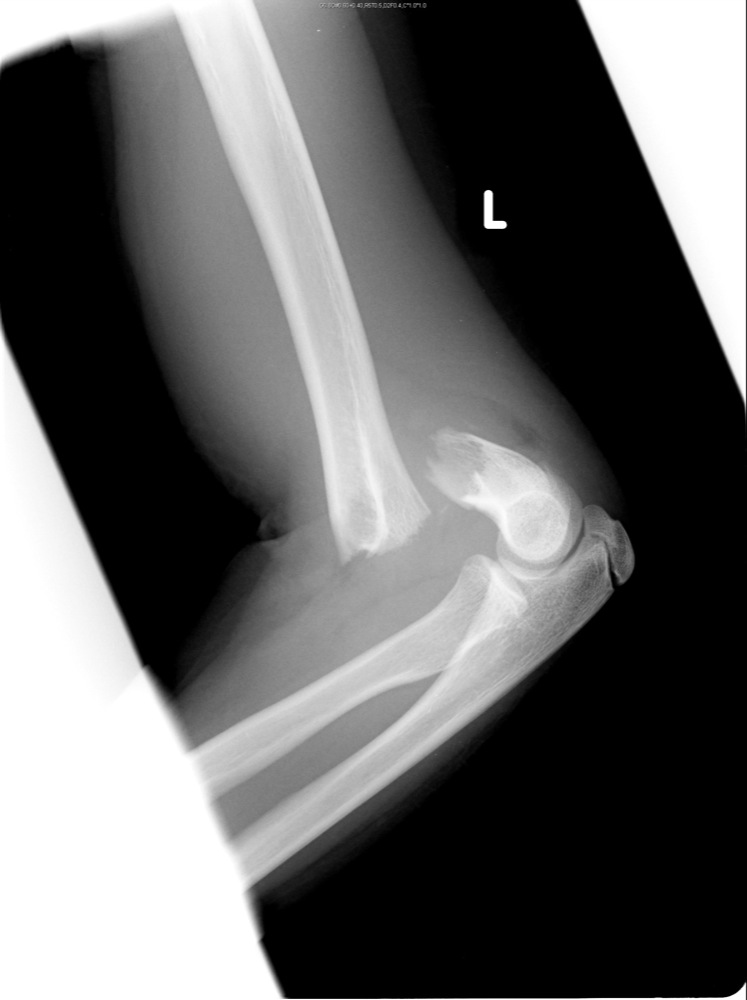

Nope. the shock tends to break wrists as they are the weakest in the chain. I knew a guy who lived on a long country road and got tired of "Mailbox Baseball" taking out his mailboxes. He was a welder/fabricator and sunk an I-beam into the ground and set with concrete. He built a wood box around it to disguise it as a wood post. He then formed a 3/8" steel plate horseshoe shaped and welded it to a plate that was welded to the i-beam. When the kids drove by the next night, he heard the familiar roar of the engine building speed towards his mailbox to hear the "ping" of aluminum baseball bat hitting 3/8" steel. It shattered both the kid's wrists. Kid was an all-county baseball player, too.